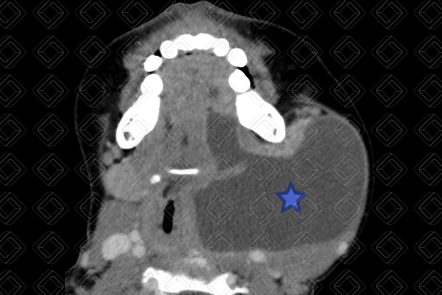

Descrição das figuras 3, 4 e 5: Tomografia computadorizada do pescoço após administração do contraste venoso, evidenciando rânula mergulhante. Observe a formação cística (asteriscos) no espaço sublingual (seta vermelha) esquerdo, estendo para região submentoniana e submandibular deste lado devido à falha na musculatura milo-hioidea. Legenda: GH = gênio-hioideo; G = genioglosso; M = milo-hioideo; D = digástrico.

• Mergulhante : A rânula profunda ou mergulhante acomete o espaço sublingual com extensão para o músculo milo-hioide. Ao exame físico, apresenta-se como uma "massa" na região submandibular ou submentoniana, podendo ou não exibir abaulamento do assoalho bucal associado.

• Tomografia computadorizada do pescoço: Apresenta-se como cisto, bem definido e bem delimitado, homogêneo, com baixa atenuação central, com paredes finas e bem identificadas, que podem realçar pelo meio de contraste (figura 2).